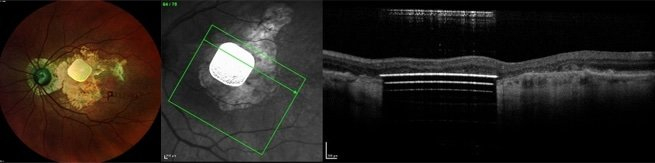

黄斑病变(AMD),也是困扰很多老年人的一种眼疾。

当黄斑慢慢侵蚀人眼,患者视觉就会变模糊,或眼前出现甩不掉的黑点,AR 隐形眼镜公司 Innovega 曾通过其人工晶体 iOptik 来治疗这个问题。不过另一家名为 Pixium Vision 的法国公司更落地。

早在 2018 年,它们的小型无线光伏视网膜下植入物 PRIMA 就被 FDA 批准开始临床研究。

这是一种由无线视网膜下植入物和增强现实眼镜组合而成的‘仿生眼’。

而且,它比 Argus II 更小、更简单、更便宜,还无需动脑部手术。

2019 年,法国 5 名患有晚期干性 AMD 的患者植入 PRIMA 的 12 个月数据表明,所有人的视网膜中央都成功引发了光感。

12 个月后,大多数患者可以识别字母,还有一定的字母序列,且没有与设备相关的不良反应,现在,他们正在欧洲和美国进行可行性试验。

PRIMA 为那些失去视力的老年人们,创造了一个仿生视觉的世界。